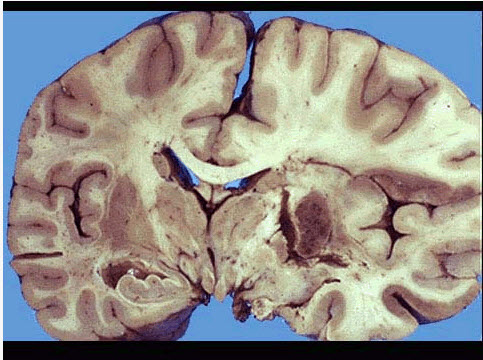

图为脑梗死的肉眼及镜下观,叙述不正确的是()

A.多为贫血性梗死

B.若梗死区血供部分恢复,血液再灌注则可转变为出血性梗死

C.矢状窦血栓形成造成的梗死为出血性梗死

D.脑梗死时组织坏死多属于液化性坏死

E.大脑中动脉栓塞导致的脑梗死其栓子多来自于门静脉系统